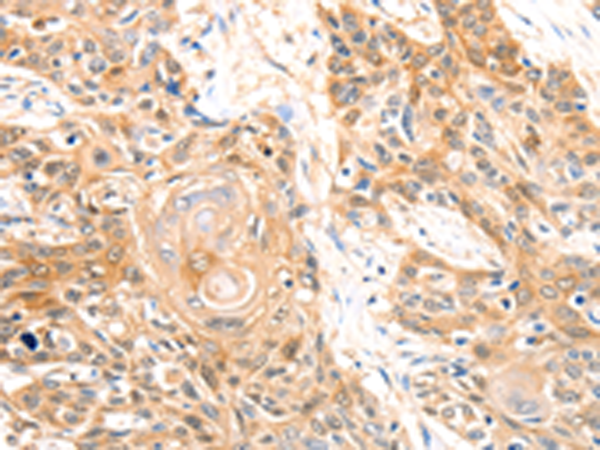

分类: 科研抗体货号: P00199别名: DTL; BAFF; BLYS; CD257; TALL1; THANK; ZTNF4; TALL-1; TNFSF20应用: WB,IHC反应种属: Human